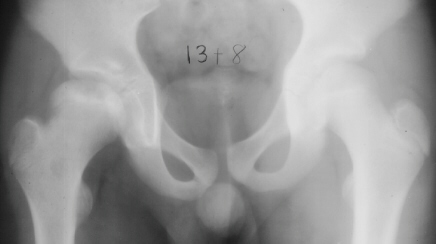

The parents first noted at the time the patient was 10y and 9 m old that he would limp on the right side after a full day of activity. He also started to have a occasional hip pain. Since the hip pain became progressively worse, he visited local clinics and was referred to AIDI at the age of 11y and 3 m. At the first examination abduction was 40 degrees bilaterally but internal rotation was limited to 0 degree on the right. The leg lengths were equal and no Trendelenburg sign was observed. X-ray showed the decreased epiphyseal height and medial joint opening. Snyder sling was started. At 12 years of age, internal rotation was still limited 20 degrees compared to 35 degrees on the left side but the left hip pain was asymptomatic. At 13 years of age, X-ray showed the regenerated head, so the Snyder sling was stopped and weight bearing was started. The Snyder sling had been applied for 2 years. At 16 years of age, ten degrees limitation of internal rotation as compared to the opposite side was still observed but the patient was asymptomatic.

11 yrs 3 mos, , 12 yrs, 13 yrs 8 mos , 17 yrs , 18 yrs.